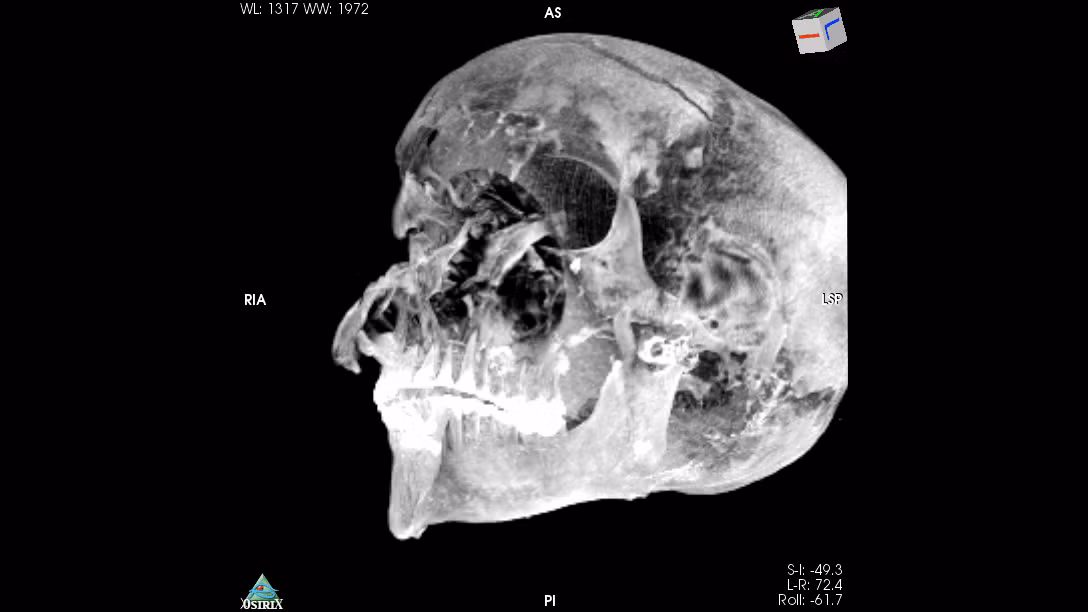

Kết quả kiểm tra xác ướp của pharaoh Seqenenre Taa II cho thấy ông có các vết thương ở đầu, mặt và nhiều vị trí khác trên cơ thể.

Các nhà nghiên cứu đã so sánh những vết thương do các loại vũ khí của người Hyksos gây ra và phát hiện pharaoh Seqenenre Taa II bị tấn công, tra tấn và giết hại bằng một chiếc rìu, một ngọn giáo và một vài con dao găm.

Đôi tay biến dạng của pharaoh Seqenenre Taa II cho thấy nhà vua Ai Cập có thể đã bị binh sĩ Hyksos bắt trên chiến trường. Sau đó, 2 tay của ông bị trói sau lưng.

Điều này khiến khiến pharaoh Seqenenre Taa II không thể tránh được cú tấn công chí mạng vào phần đầu. Vào thời điểm tử vong, pharaoh Seqenenre Taa II khoảng 40 tuổi.